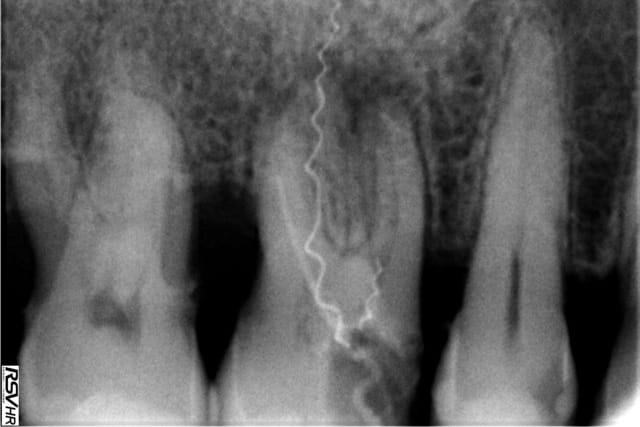

Ah bah mince, j'ai pété un lentulo ;)

Aahh joli. Il semble qu'il y a eu une erreur du sens de rotation, ce qui aurait vissé le lentulo dans le tisseu osseux, et surtout qui aurait étiré les spires jusqu'à fracture, le tout en 1 seconde de temps.